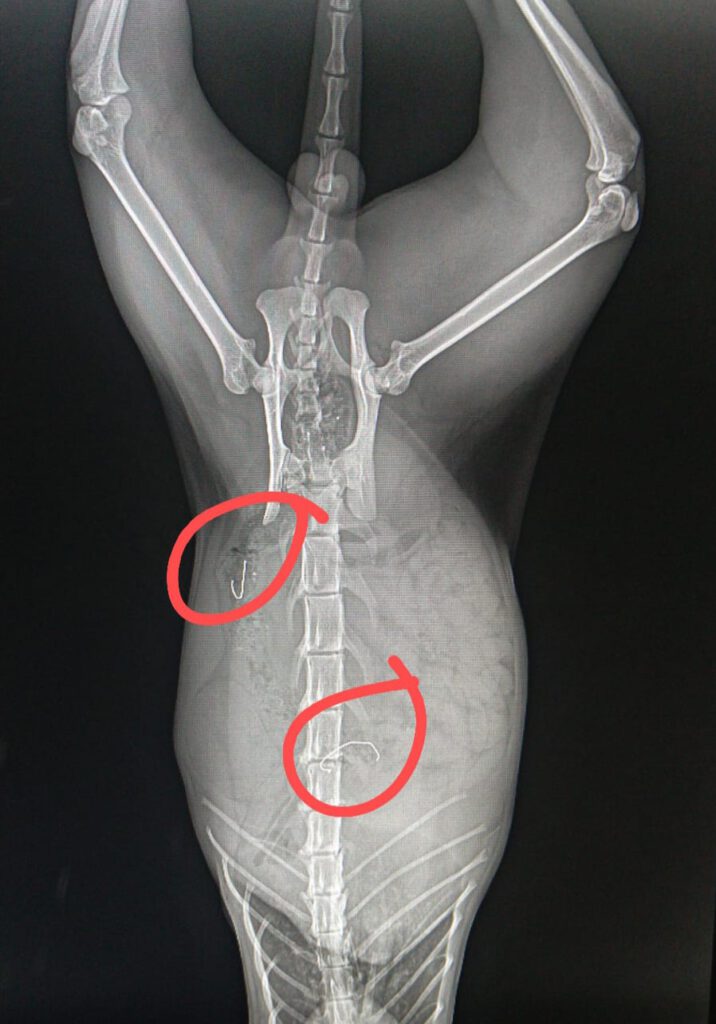

In der anschließenden Behandlung stellte sich heraus, dass die Katze neben erheblichen Verletzungen an der Pfote auch metallische Gegenstände, vermutlich die Befestigung des Köders, in Körper hatte. Die Veröffentlichung der Röntgenbilder wurden vom Tierarzt genehmigt.